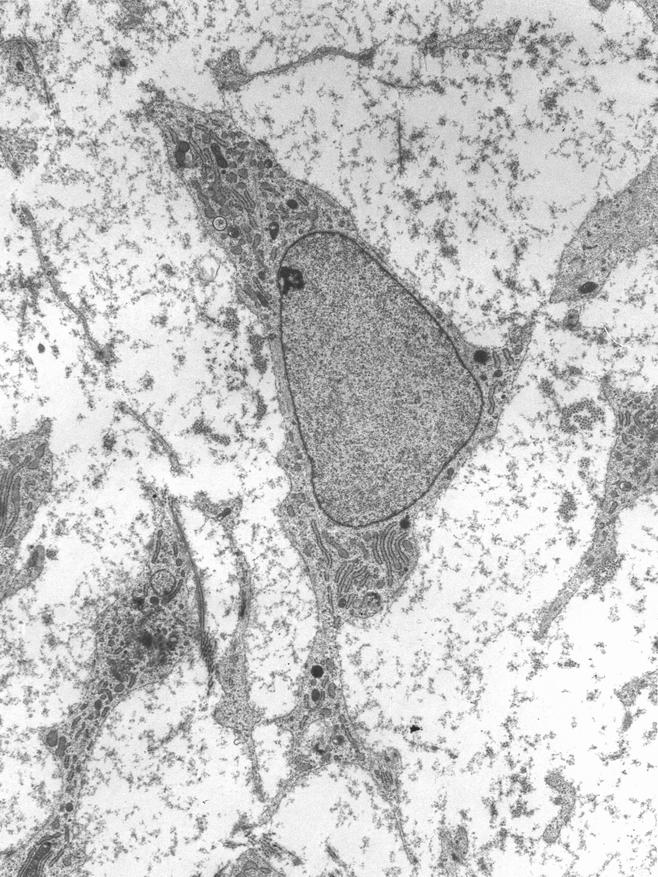

Одна из наиболее многообещающих областей медицины — регенеративная медицина, которая использует стволовые клетки для восстановления поврежденных тканей и органов. Стволовые клетки обладают уникальной способностью к самообновлению и дифференциации в различные типы тканей.

Недавно учёные из России, специализирующиеся на молекулярной биологии, совершили значимое открытие: им удалось выяснить, что срок жизнеспособности культур мезенхимальных стволовых клеток (MSC) можно увеличить в два или даже в три раза путём искусственного удлинения их теломер. Это открытие имеет огромное значение для будущих антивозрастных терапий, так как показывает, что теоретически можно замедлить или даже остановить клеточное старение на определенном уровне.